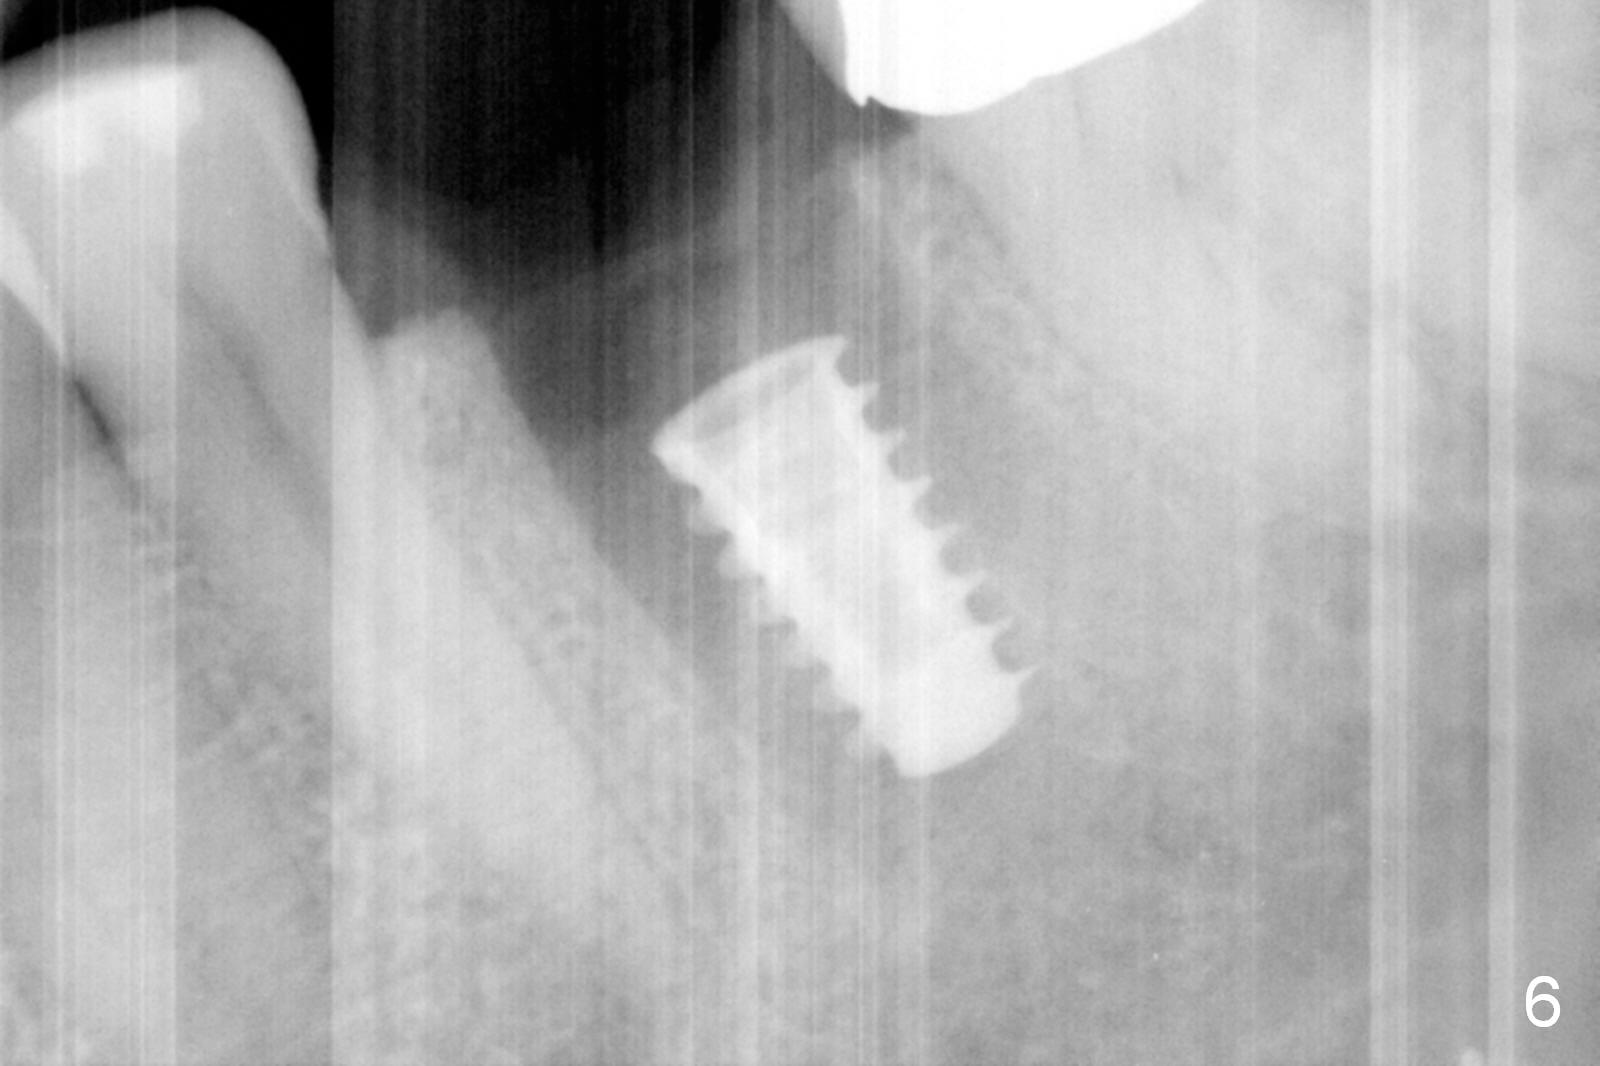

The tooth #19 is easy to get loose, but it cannot be luxated.  After sectioning and extraction (Clindamycin), the septum is found to be thin (Fig.4).  A surgical fissure bur is used to initiate osteotomy, followed by 1.6 mm pilot drill.  It is difficult to use Marking bur (wobbling over the basically pointed septum).  It is impossible to use 4.3 mm Magic Drill (MD, one drill system), since it jumps.  The smallest MD has to be used (2.8 mm).  When the next drill (3.3 mm) is being used for 13 mm with stopper (Fig.5), the patient experiences transient pain.  The depth is suggested from the design in Fig.2.  The thin septum appears not to be a reliable landmark.  When block anesthesia is administered, the initial depth should be shortened.  The drill appears to be close to the Inferior Alveolar Canal (Fig.5).  Then the depth changes to 11 mm with the following drills (3.8 and 4.3).  The mesial and distal walls of the septum are gradually perforated.  A 5x9 mm dummy implant is placed only after using 4.8 mm drill (Fig.6).  The implant appears to be short.  When a longer implant is placed (5x11 mm), it does not easily enter the osteotomy, either sliding into the mesial or distal socket with the implant separating from the implant driver.  It appears that a premount implant is appropriate in this situation.  When the 5x11 mm implant is finally seated with stability, it is 6 mm apical to the gingival margin.  The longest cuff of IBS abutment is 4 mm.  A longer implant is needed (Fig.7, 5x13 mm).  Placement is not easy as mentioned above.  Insertion torque is <20 Ncm when the patient experience a little discomfort.  A 6.5x4(4) mm pair abutment is placed (A), apparently proper for restoration.  Allograft is placed (Fig.8 *) prior to immediate provisional.  The patient complains of bad smell from the site 24 days postop.  When the provisional is removed, the abutment is found to be mobile.  When the latter is removed with local anesthesia, bone graft granules are attached to the socket above the lightly mobile implant (Fig.9).  In fact the latter appears to be stable after a few turns by finger.  A healing screw is placed; the socket is closed with collagen plug and 4-0 Chromic gut sutures (Fig.10).  It appears that a larger implant should have been used to achieve higher torque.  Two months later (3 months postop), the coronal end of the implant is partially exposed.  A 5x4 mm healing abutment is placed.  It appears that the implant is stable.  The implant appears to have osteointegrated 4 months postop (Fig.11).  Impression is taken.